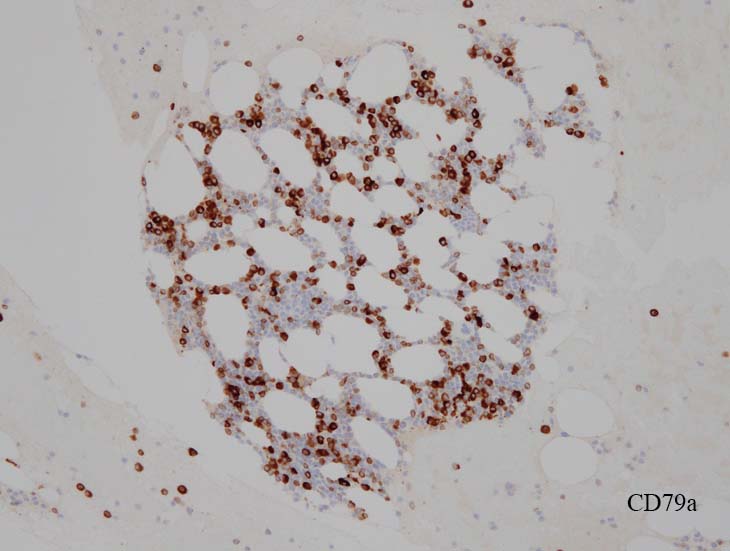

blastic cellsは, CD45+, CD34+, CD38+, TdT+, CD7+, HLA-DR+, CD123+. cCD3-, sCD3-(FCM), CD20-, CD19-とCD79a-(?) (plasma cellが陽性でIHCでは判定が難しい), MPO-.

CD3-, CD79aは増加しているplasma cellsが陽性で判定が難しい. CD10-, MPO-. (CD10は画像欠)

CD138陽性細胞が増加している. CD19陽性細胞が多く認められ, 明かなkappa, lambda restrictionは見られない. polyclonal proliferationと考えられる.